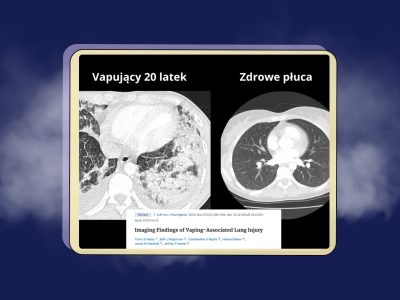

O szkodliwości zwykłych papierosów wiemy wiele – są one dostępne na rynku od lat i ich negatywny wpływ na ludzkie zdrowie został dość obszernie przebadany. E-papierosy są dostępne znacznie krócej, a poszczególne ich rodzaje znacznie się od siebie różnią i mają różne składy. Te czynniki powodują, że...